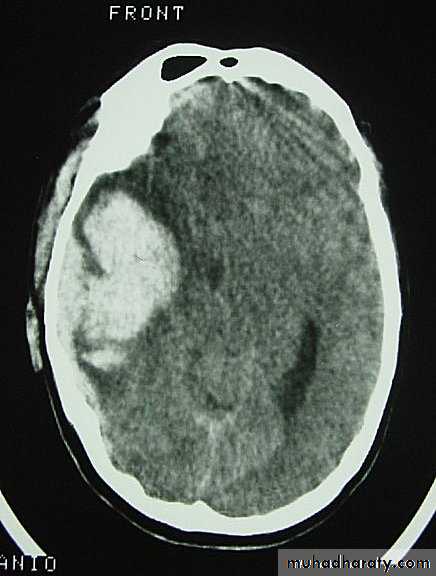

c. Intracerebral Haematoma

This is the least common of traumatic haematoma.

They are due to areas of traumatic contusion coalescing into a contusional haematoma.

Disrupted cerebral tissue release thromboplastins that potentiate haemorrhage.

CT scan: appear as hyperdence lesions with associated mass effect and midline shift.

Large intracerebral haematomas should be evacuated unless the patient’s neurological state is improving.

Small inracerebral haematomas may not require removal, but be aware that they can expand.